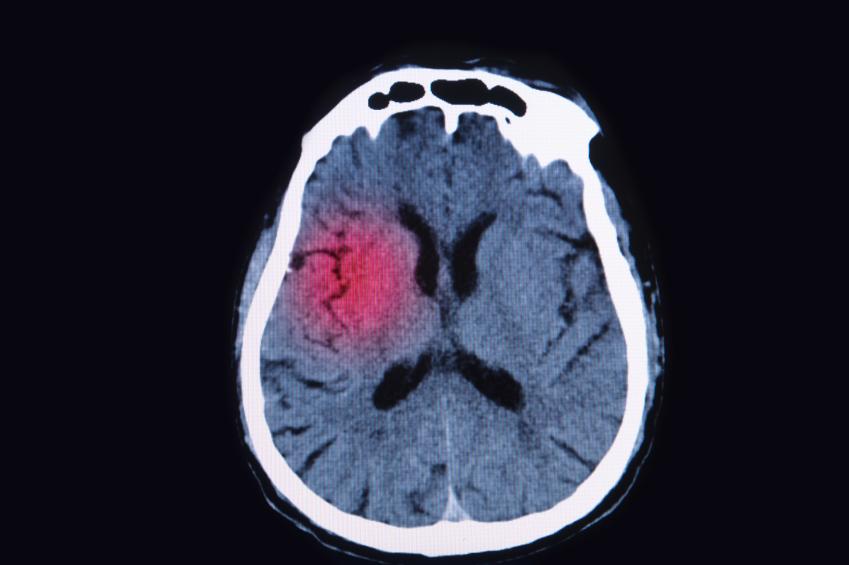

Un aneurisma es la dilatación de una arteria que termina formando una bolsa o bulto de sangre cuyo principal peligro es que el mismo se reviente, esta rotura tiene lugar por algún golpe, herida o ulceración. Cuando un aneurisma revienta se produce una hemorragia interna que puede comprometer seriamente la vida del paciente de no ser detenida a tiempo. Los aneurismas pueden presentarse en la aorta, el cerebro, los intestinos o el bazo, y aunque en algunos casos son asintomáticos llevar un buen control médico y reducir al mínimo los factores de riesgo son claves para su prevención y tratamiento. En unComo.com te explicamos con detalle cómo tratar un aneurisma.